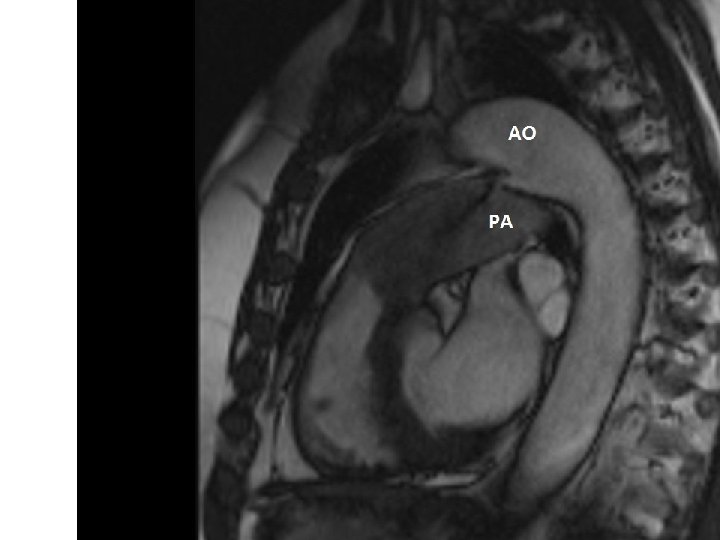

Transpozice velkých cév – Jatene operace